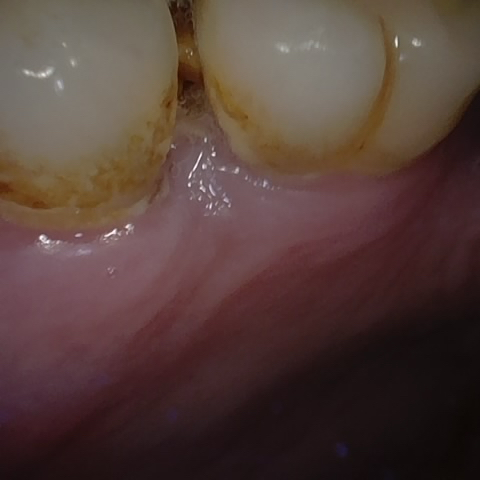

Annotated as "Good"